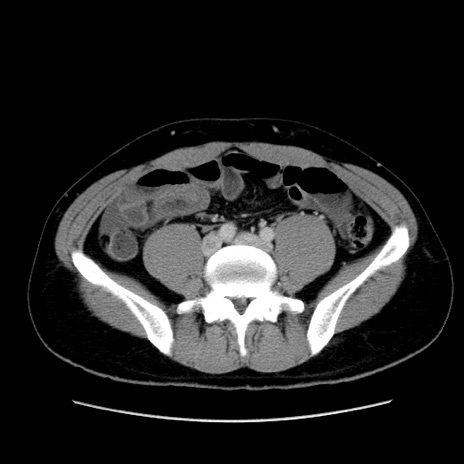

冠状断像

【症例】20歳代 男性

【主訴】心窩部痛

【現病歴】今朝より上腹部痛あり。一旦軽快していたが再度出現したため救急要請。昨日夕に白身の魚を含む刺身を食べた。

【身体所見】BP 136/89mmHg、HR 74/min、BT 37.0℃、腹部:膨満、軟、心窩部に圧痛あり。反跳痛なし、筋性防御なし、腸雑音やや亢進あり。

【データ】WBC 17700、CRP 0.48